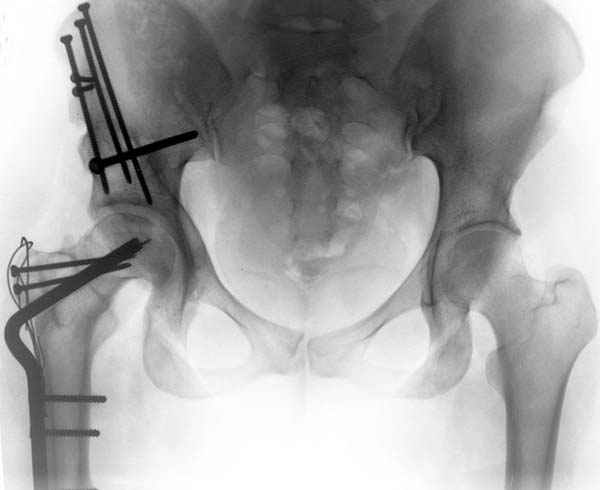

Рис.1 Трехмерная модель тазобедренного сустава с аналогом связки головки бедра. Заметно, что из торца головки выходит капроновый шнур, который с одной стороны прикрепляется к ножке бедренной части модели, а другой его конец, проходя через головку и прикрепляется к вертлужной части модели. Динамометр оказывается не нагруженным, так как аналог связки головки бедра замыкает подвижный узел модели во фронтальной плоскости.

Рис.2 Та же трехмерная модель тазобедренного сустава без аналога связки головки бедра. Пружина динамометра удерживает тазовую часть модели от опрокидывания, поддерживая стабильность так же, как отводящие мышцы обеспечивают ее в отсутствии связки головки бедра.